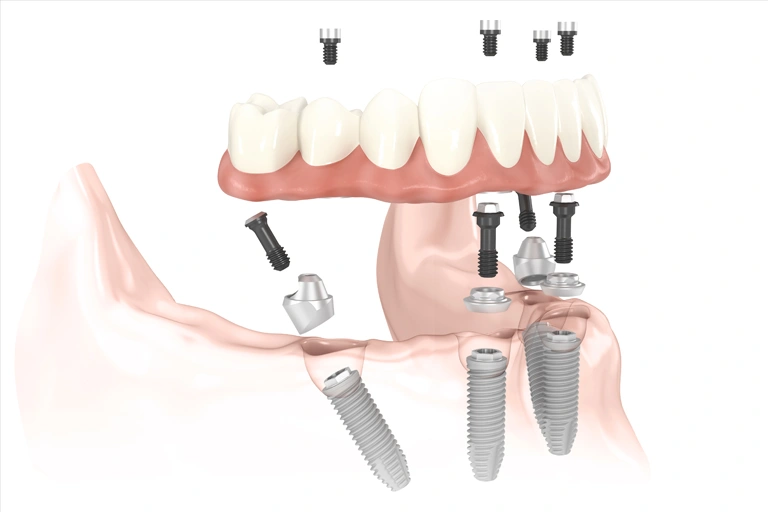

All-on-4 or All-on-6 dental implants are a highly esthetic and comfortable solution for anyone wishing to replace their denture or failing teeth with a fixed arch of teeth. Our Winchester, VA Dental Implant Center only uses the highest top-quality dental implants and components backed by clinical research.

With conventional implants, also called single tooth implants (click here to learn more), you need 12 implants to support the crowns replacing your missing teeth. This means the cost of treatment is very high. Conventional or traditional dental implant treatments also increase the likelihood of requiring a dental bone graft before implants can be placed. With an All-on-4 or All-on-6 dental implant procedure we only require 4 or 6 dental implants to secure a full arch of teeth.

All-on-4 or All-on-6 is typically much more cost effective than conventional implant treatment, as it only requires 4 to 6 implants and bone grafting can often be avoided. Since Dr. Oestervemb does the whole procedure from start to finish in house, our fees are normally significantly less than if you have to see multiple dentist. One for the implant placement, and another dentist for the placement of the bridge. This is also more convenient for you as a patient as there is only 1 point of contact. Dr. Oestervemb offers free consults and always bases his price on your specific needs to help keep cost down as much as possible.

- You, as a patient, need to make sure you know what you are getting. Often times patients only get a plastic/acrylic bridge to replace the teeth. We only use an all porcelain bridge for our all-on-four and all-on-six patients since, this has a longer survival rate, better esthetics and is easier to keep clean.